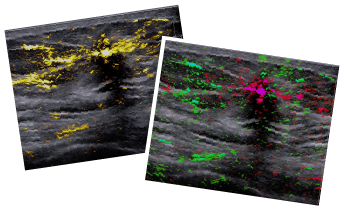

Pioneered by Seno Medical, Opto-Acoustic/Ultrasound (OA/US) shines a new light on breast cancer diagnostics, enabling a real-time assessment to differentiate malignant from benign breast tissue.

Without dyes, radiation, or invasive procedures, Imagio® provides the clinician an immediate, objective diagnosis leveraging the AI-driven clinical decision support tool, SenoGram®.

See Imagio® and SenoGram® in action with a clinical demonstration of OA/US technology and examples of images that can differentiate malignant and benign breast tissue on screen and in color, with the painless, real-time OA/US scan.